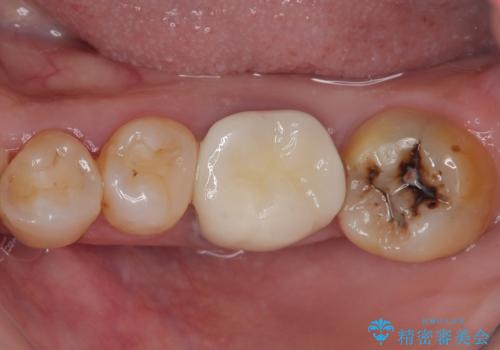

下顎大臼歯の再根管治療とオールセラミッククラウンによる補綴治療